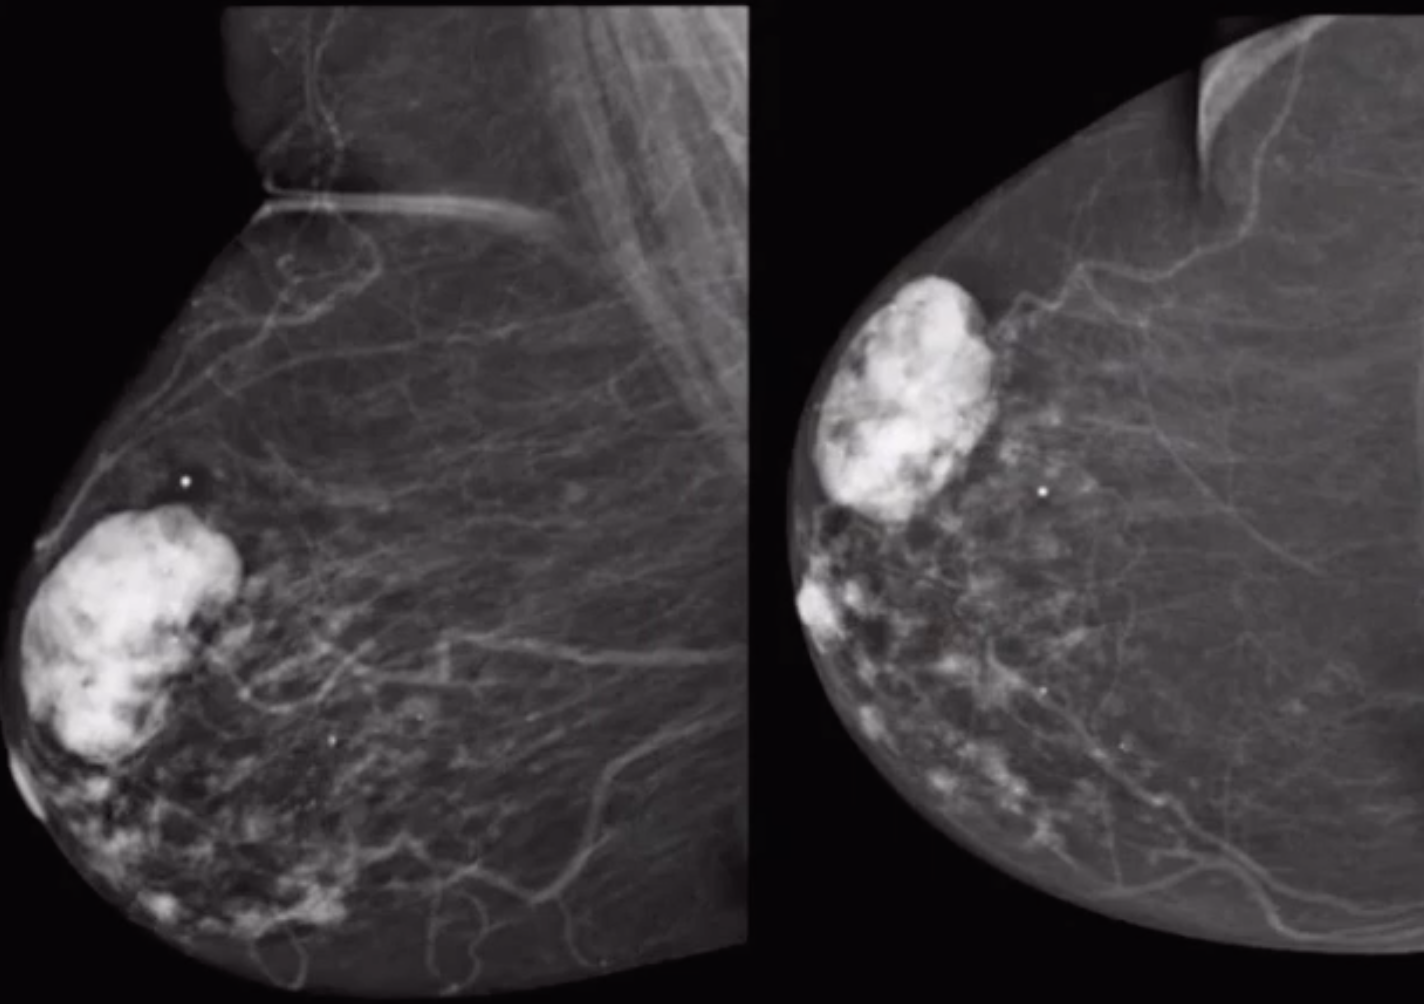

• Round well circumscribed mass with central scar

• If seen in an older person it will have bulky popcorn calcs, with increased calcs in it over time